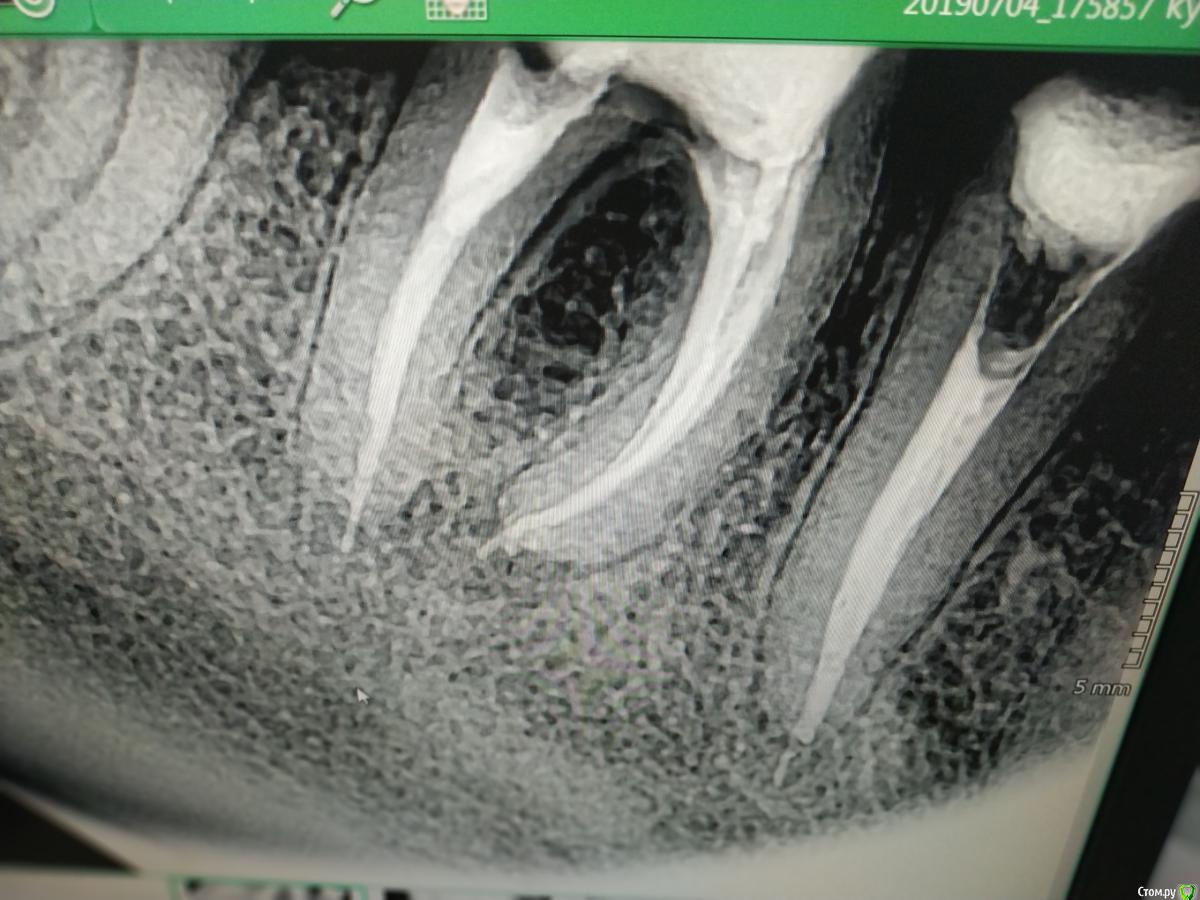

kuziy12 Опубликовано 20 июля, 2019 Автор Поделиться Опубликовано 20 июля, 2019 (изменено) Лето, хорошо... Начнем с хорошего..Жесть чуть позже. Обратилась женщина с 4.5, 4.6. Рекомендовал удалить 4.5, туда имплантация, 4.6 пробовать сохранять. Решили сохранять оба.Изначальная ситуация: Распломбировка, обработка машинными: 4.5 - до 30.04, .4.6 - до 25.04. Пульпосептин на 3 дня, пломбировка, культевая в 4.5, в 4.6 штифт и пломба. Дальше коронки МК связанные между собой. Надеюсь укрепит 4.5. Переживаю больше за его тонкие стенки. В храм сходил - свечку поставил. Вопрос: на сколько по времени ставите пульпосептин(если пользуетесь) при пульпитах, хронических, обострениях? Изменено 20 июля, 2019 пользователем kuziy12 Ссылка на комментарий

vse32 Опубликовано 20 июля, 2019 Поделиться Опубликовано 20 июля, 2019 Если честно, очень переживаю за бифуркацию 46. Думаю, через год вы там увидите неприятное разряжение. Тьфу-тьфу-тьфу конечно. Так что для меня тут более слабое звено 46, а не 45. Ссылка на комментарий

vse32 Опубликовано 20 июля, 2019 Поделиться Опубликовано 20 июля, 2019 Вы не поняли. Я не про то сейчас мне видится из-за жёсткости или резкости. А из-за очень тонкого дна полости зуба, отделяющего ее от фурки. Обычно там уже все сильно инфицирование. Что впоследствии даёт проблемы - разряжение в бифуркации Ссылка на комментарий

kuziy12 Опубликовано 20 июля, 2019 Автор Поделиться Опубликовано 20 июля, 2019 (изменено) Вы не поняли. Я не про то сейчас мне видится из-за жёсткости или резкости. А из-за очень тонкого дна полости зуба, отделяющего ее от фурки. Обычно там уже все сильно инфицирование. Что впоследствии даёт проблемы - разряжение в бифуркацииПонял вас. Но тут аргумент: с такими зубами, как на первом снимке она ходила 1.5 года. Не знаю только в пользу он или нетP/s: в л.с написал вам Изменено 20 июля, 2019 пользователем kuziy12 Ссылка на комментарий